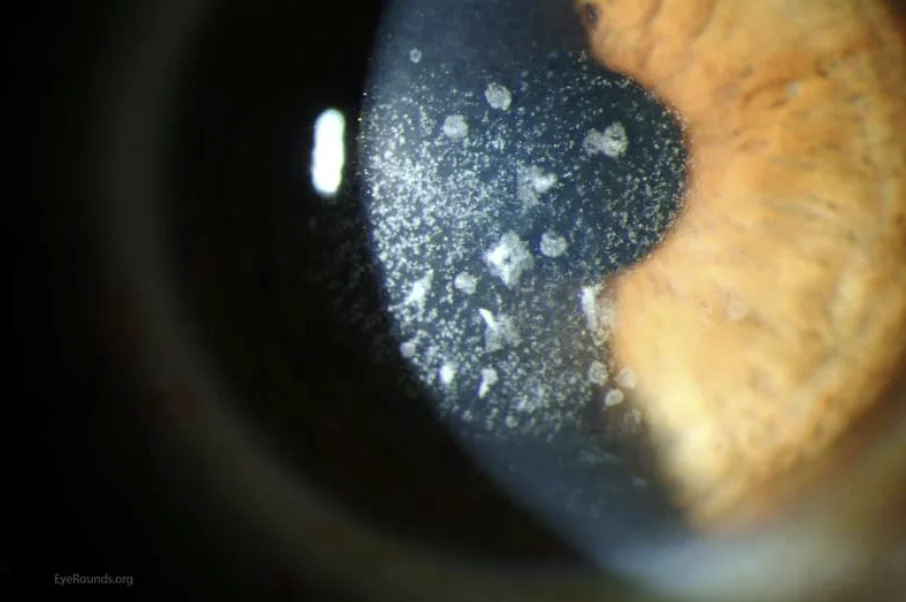

제가 라식이나 라섹 수술을 상담할 때 이형접합자를 강조하는 이유가 있습니다. 동형접합자의 경우에는 대개 10세 이전에 이미 눈에 띄는 혼탁 증상이 나타납니다. 안과에서 간단한 현미경 검사만으로도 바로 확인이 가능하기 때문에 굳이 유전자 검사를 따로 하지 않아도 금방 찾아낼 수 있습니다.

하지만 이형접합자는 다릅니다. 이 유형은 나이가 들 때까지도 각막 안에 숨어 있어서 겉으로는 전혀 티가 나지 않는 경우가 많습니다. 본인조차 모르고 지내다가 유전자 검사를 해보고 나서야 발견되는 경우가 대부분이지요. 만약 이를 모른 채 각막을 깎는 수술을 받게 되면 병증이 급격히 진행될 수 있어 매우 위험합니다.